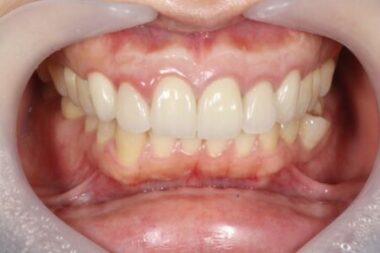

その後も3ヶ月、1年と経過を追って確認した結果、現在に至るまで外科手術による瘢痕はほとんど見られず、

美しい歯茎のラインを維持したまま、無事に治療を完了することができました。

画像がこちらになります。

また、心配されていた審美的な問題もなく、自然な見た目を保ったまま治療を終えることができました。